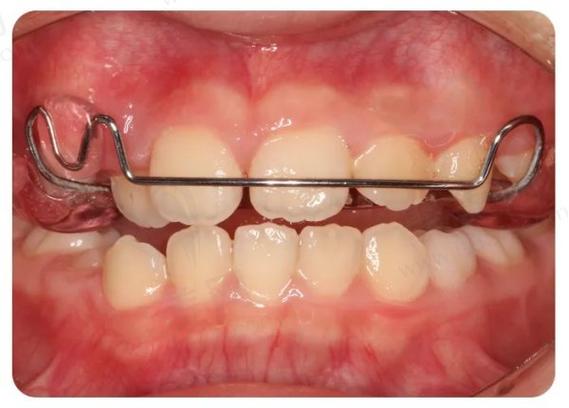

(图片来源网络,侵删)- 骨开裂或骨皮质穿孔: 尤其是在上颌骨,扩弓器施加的力量过大或时间过长,可能导致牙槽骨的骨皮质(骨表面坚硬层)开裂甚至穿孔,这会破坏骨组织的完整性,影响牙齿的长期稳定性。

- 牙龈退缩和牙槽骨吸收: 牙齿过度颊侧倾斜(向脸颊方向移动)会使牙根唇侧(靠近嘴唇一侧)的牙槽骨和牙龈组织受到过度牵拉,导致牙龈退缩、牙根暴露,甚至牙槽骨进一步吸收,这不仅影响美观,还可能导致牙齿敏感、更容易龋坏和松动。

- 牙齿倾斜度过大: 扩弓主要依靠牙齿的倾斜移动来实现,过度扩弓会导致牙齿颊侧倾斜角度过大,使牙齿看起来“歪斜”,影响美观和功能。

(图片来源网络,侵删)- 颊部软组织张力过大: 牙弓过度扩大可能使颊部肌肉和软组织被过度拉伸,导致患者感觉脸颊“鼓胀”、“不自然”,甚至影响发音和进食。

牙齿过度颊倾、牙龈退缩、牙根暴露、颊部鼓胀等都会显著影响面部美观。